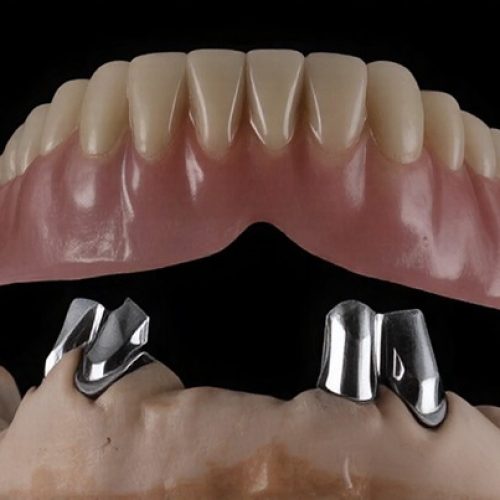

Dr Nitesh Rai, specializes in replacement of teeth with complete dentures, removable partial dentures, fixed partial dentures and Implants.

He has been actively involved in providing implant treatment for over two decades. He is also a committed academician, educating dental students and has been associated with Krishnadevaraya college of Dental sciences, Bengaluru as a Senior Professor, PG Guide and teacher in the Department of Prosthodontics, Crown and Bridge and Implant.